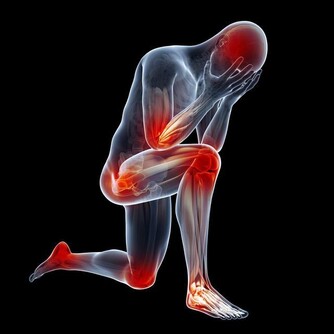

頸部不適可能在任何情況下出現,可能是上了一天班後脖子突然一陣刺痛,也可能是剛醒來後的鈍痛。如果感到脖子酸痛、僵硬,甚至發出聲響,說明頸椎正在受到折磨。

頸部是連接頭和軀幹的關鍵,頸椎受傷,就會影響到全身健康。

頸部不適有可能是意外或者退化病症(如關節炎)導致,但生活中的一些壞習慣,卻在一點點加重對脖子的傷害。

頸椎問題帶來4種健康狀況